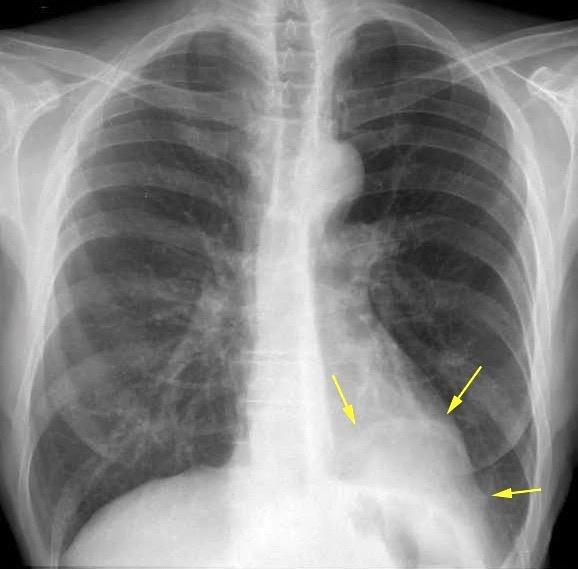

Tromboembolismo pulmonar Diafragma elevado 20%

Atelectasia crónica de LLI en paciente con enfermedad neuromuscular.